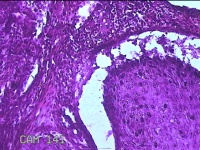

额部肿物

性别

女

年龄

32岁

临床诊断

寻常疣

一般病史

额部起疹1年,不痒。

标本名称

大体所见

灰白暗红色肿物0.7x0.5x0.2cm一个,表面光滑,切开肿物呈实性,切面灰白粉红色,质软。